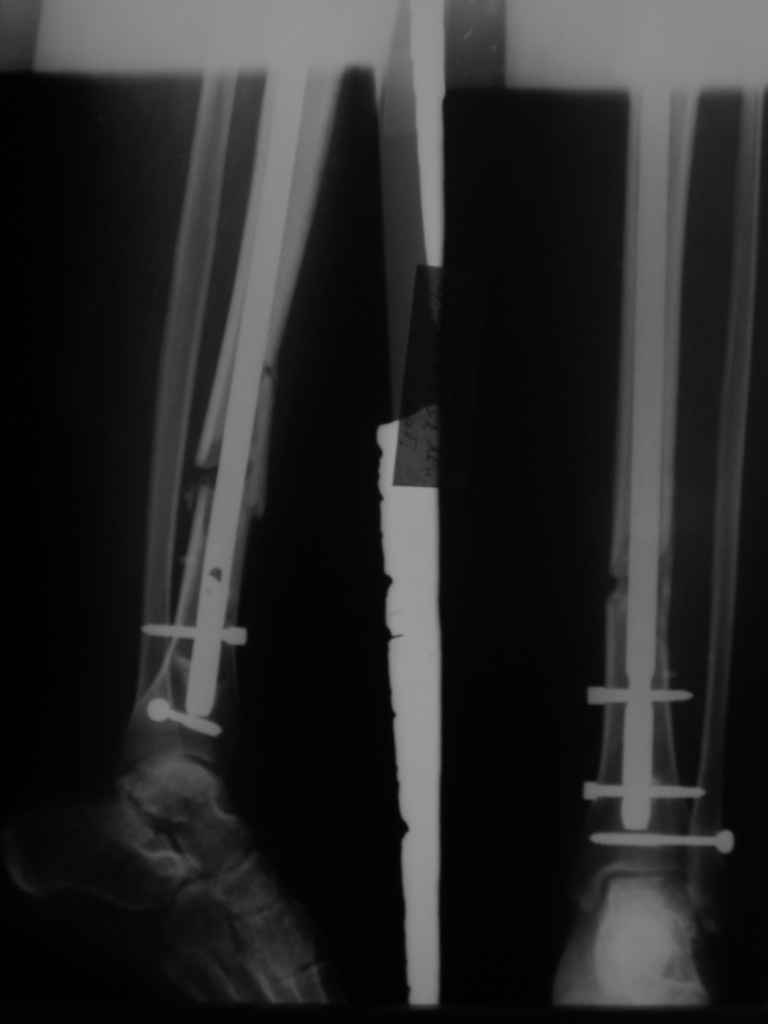

Re: неправильно фиксированный перелом

Но почему решение динамизировать на сроке 8 недель с полным удалением всех проксимальных винтов даже не рассматривается Вами? Ведь тогда нагрузка с фиксатора будет снята, и переломов металла можно будет не бояться и наступать полной нагрузкой.

Все это к тому, что те, кто занимается гвоздями и Вы в том числе можете выложить не один снимок с подобными диастазами и вальгусами-варусами, где достигнуто сращение и не получено проблем. Тогда откуда такая "адназначность" врешении об реостеосинтезе?